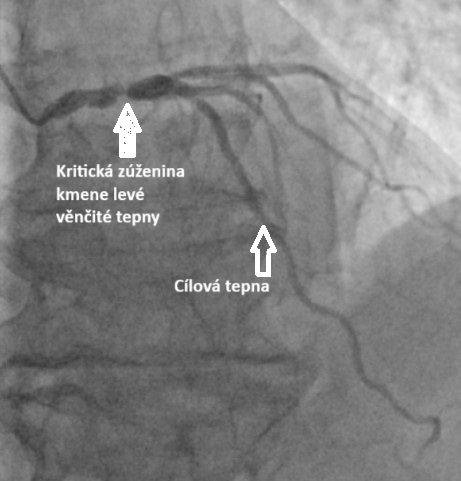

Vážení sledující. Občas hororové scénáře začínají banálním konstatován kolegy z kardiologie: „Mám tady pro tebe vhodného pacienta pro robotický MIDCABG“. Dnes to bude o relativně jednoduché operaci, která se ale může změnit v noční můru. MIDCABG je zkratka pro minimálně invazivní přímou anastomózu prsní tepny na nejdůležitější koronární tepnu. Dělá se již léta, ale hlavně je to jediná oficiálně „schválená“ roboticky asistovaná operace v kardiochirurgii.